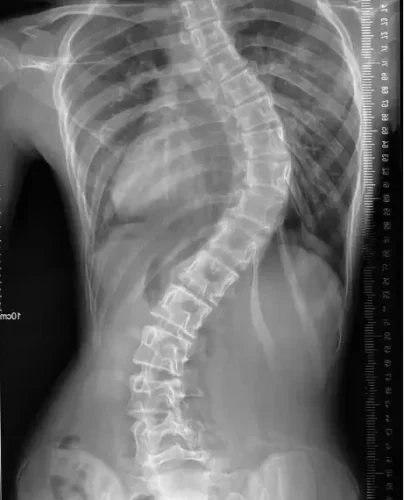

يُعدّ اعوجاج العمود الفقري، أو ما يُعرف بالجنف، من المشكلات الشائعة بين الأطفال والمراهقين. كثير من الأهل يلاحظون انحناء غير طبيعي في ظهر طفلهم، ثم يتساءلون: هل هذا الانحناء يسبب ألماً؟ وهل يمكن أن يؤثر على حياة الطفل اليومية ونشاطه؟ في هذا المقال سنجيب عن أهم الأسئلة التي تدور في ذهن الأهل ونوضح العلاقة بين الجنف والألم عند الأطفال، مع شرح طرق التشخيص والعلاج.

يعتمد الطبيب على الفحص السريري أولاً، حيث يطلب من الطفل الانحناء للأمام لملاحظة أي بروز أو عدم توازن. كما قد يطلب إجراء أشعة سينية لقياس زاوية الانحناء بدقة وتحديد إذا كان الاعوجاج خفيفاً أو متوسطاً أو شديداً.